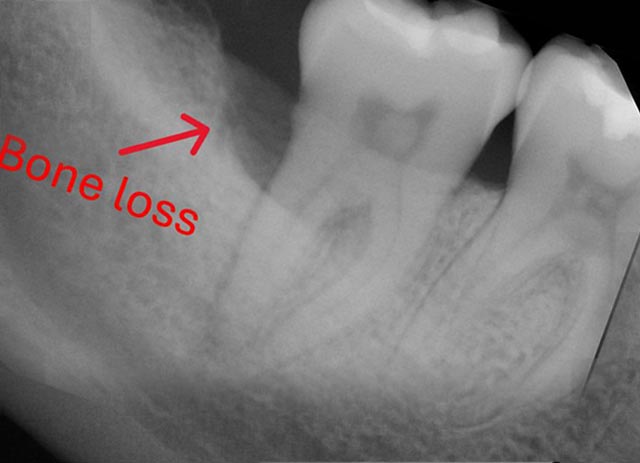

Implant Bone Grafting - Before And After

Implant bone grafting – before surgery

Implant bone grafting – after surgery